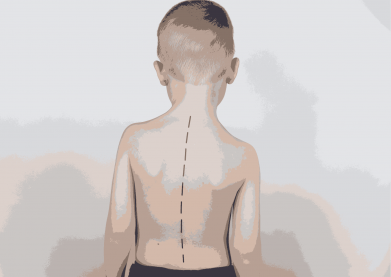

Pasak kineziterapeutės G. Damušytės, skoliozė – tai patologija, kuri pasireiškia stuburo iškrypimu į šoną. „Žiūrint į žmogų iš nugaros sveikas stuburas atrodo kaip tiesi linija. Skoliozės atveju stuburas ima krypti į šoną. Iškrypimai gali vystytis tiek krūtininėje, tiek juosmeninėje stuburo dalyje. Deformacija konstatuojama tada, kai stuburo pakrypimo laipsnis pagal vertinimo skalę pasiekia 10 laipsnių ir daugiau. Ligai progresuojant pakinta laikysena, atsiranda ryški asimetrija“, – sako specialistė.

„Bene pirmiausia apie galimą skoliozę sufleruoja pečių ir klubų asimetrija, kuri didėja priklausomai nuo ligos progresavimo. Paprastai vienoje kūno pusėje pastebimas labiau atsikišęs petys ar klubas. Neretai skoliozę turintys žmonės skundžiasi, kad sunku rasti tinkančius drabužius, šie tarsi „negula“ ant jų kūno. Pasilenkus į priekį, vienoje stuburo pusėje išryškėja kupra, kitoje – įduba, iš priekio gali būti matoma šonkaulių lanko asimetrija. Neretai stuburo iškrypimas būna tiesiog matomas akimis“, – sako G. Damušytė.